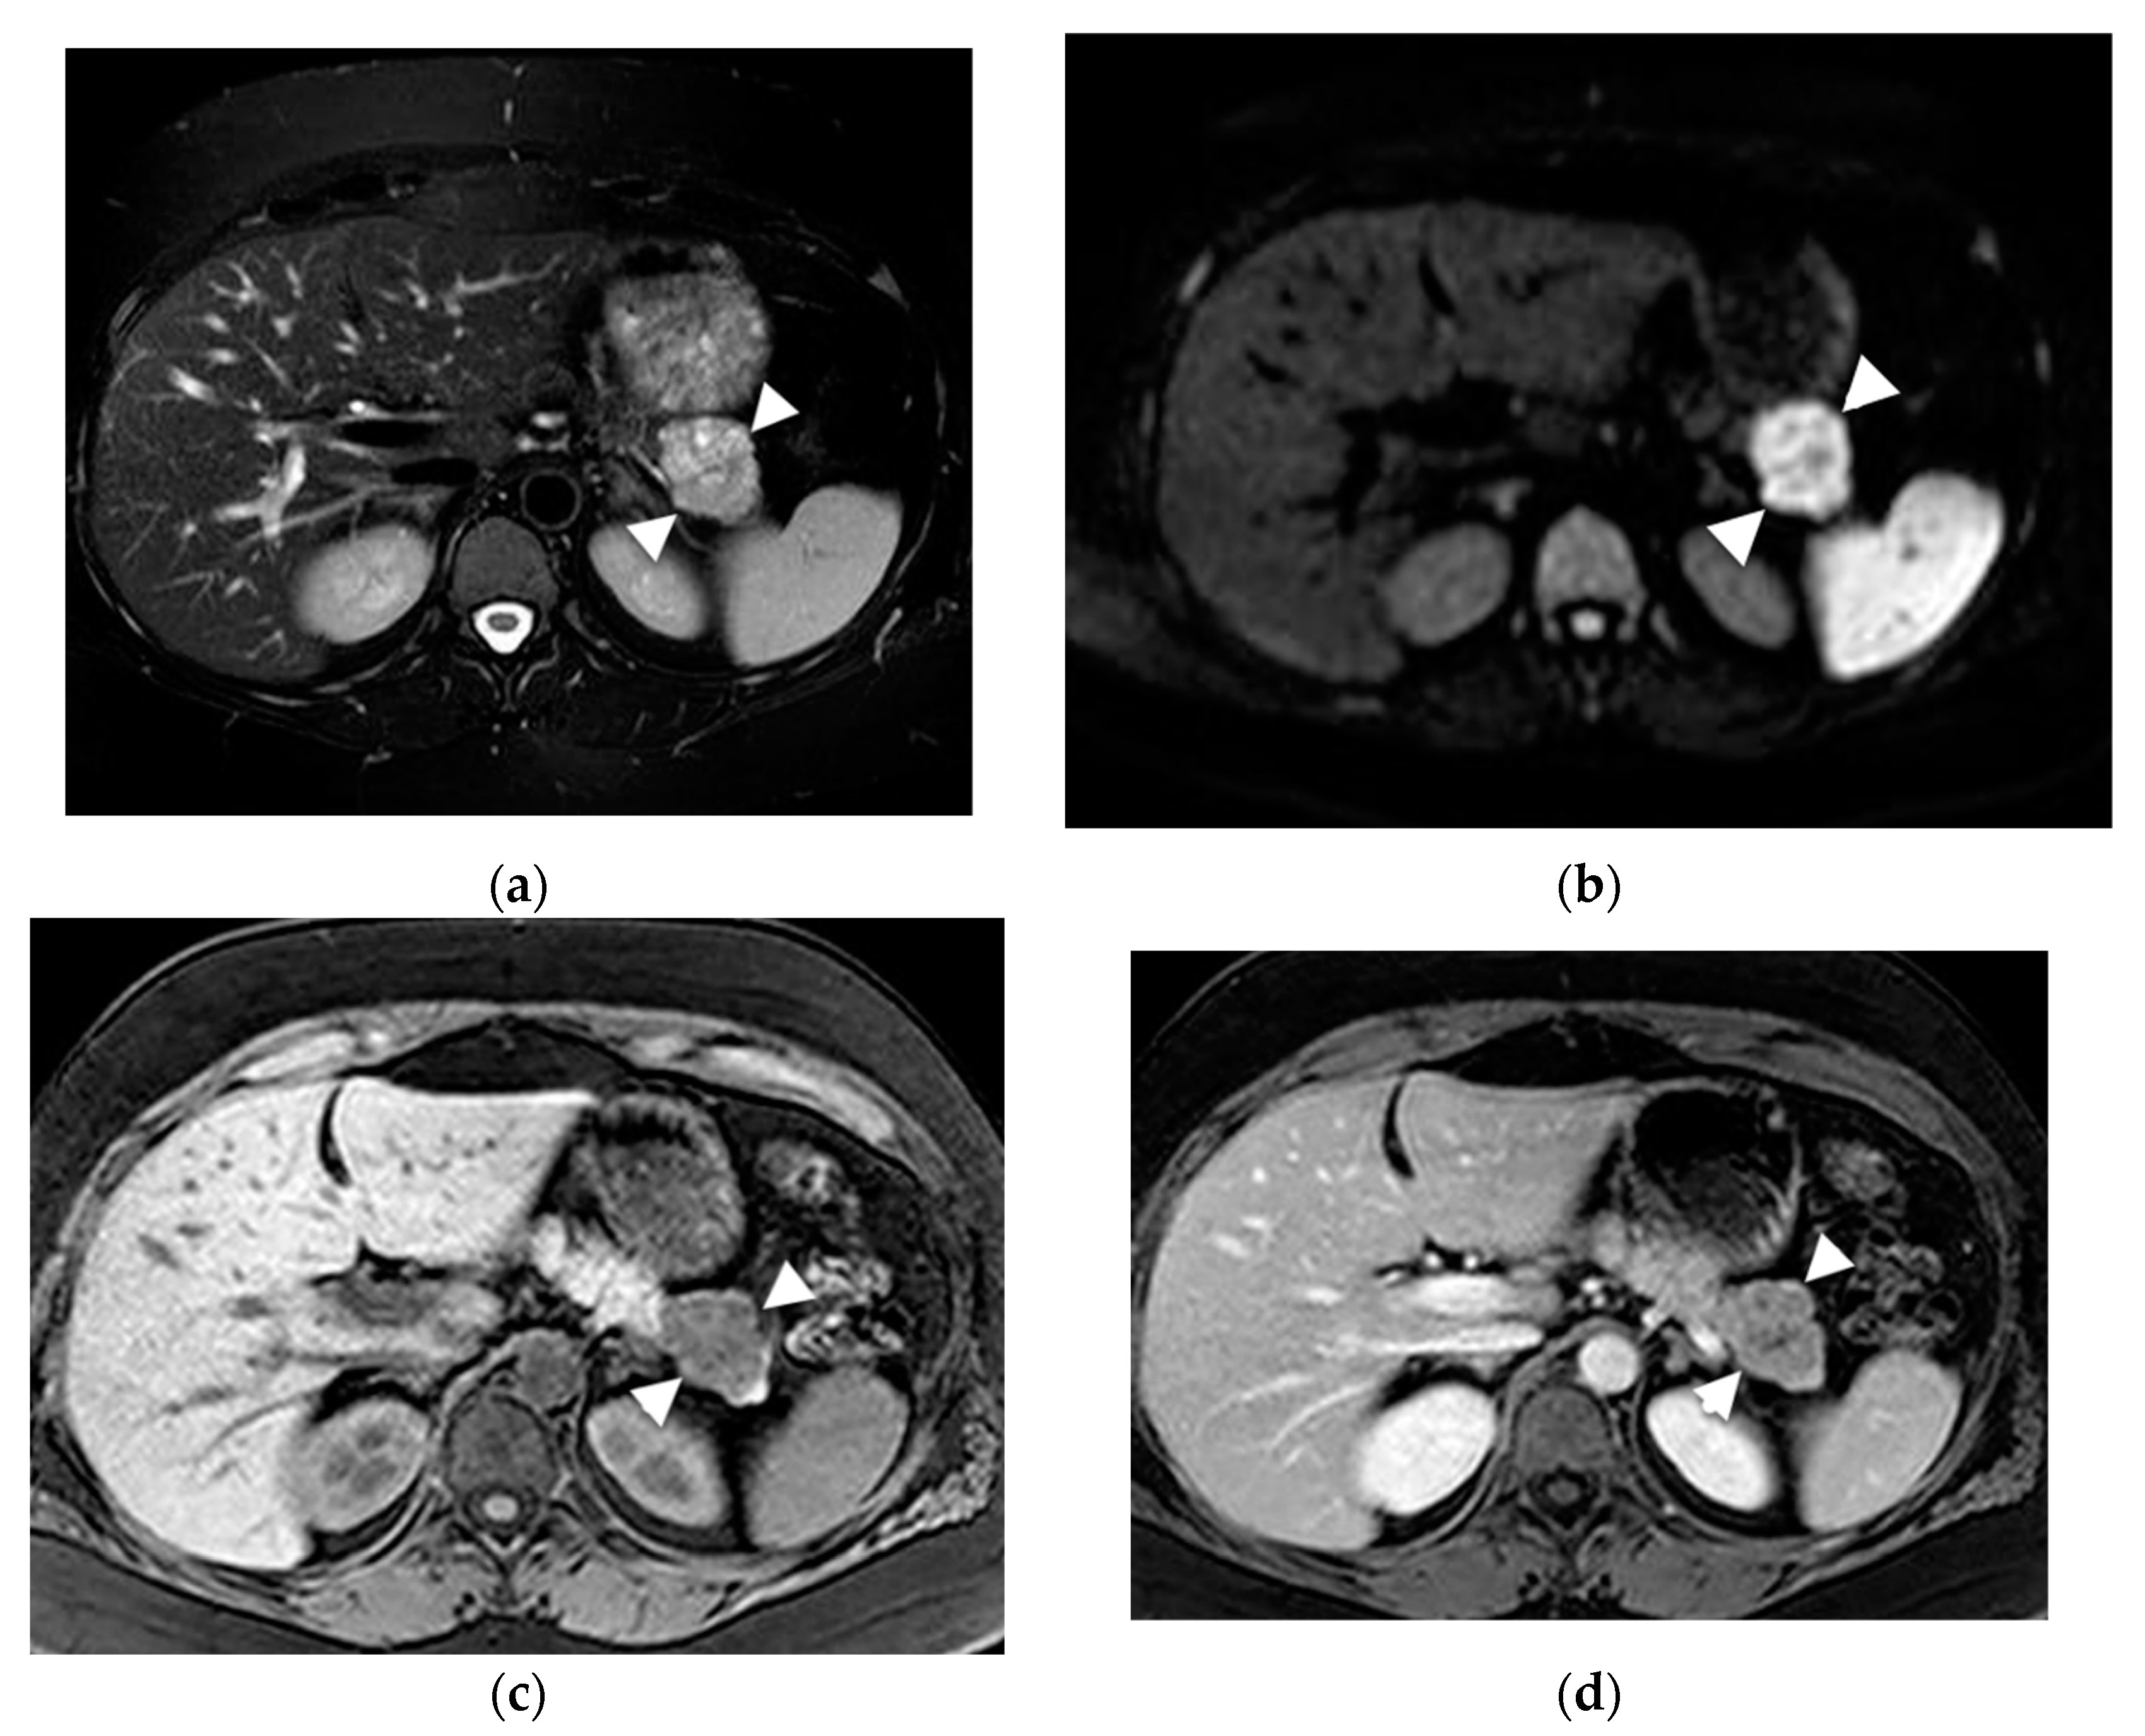

6.1. Intraductal Papillary Mucinous Neoplasm (IPMN)